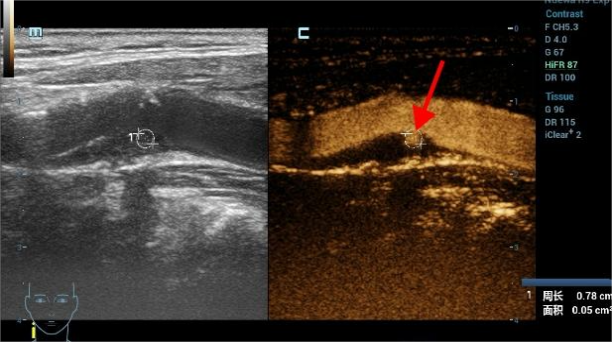

超声造影是在常规超声检查的基础上,通过静脉注射超声造影剂,增强对比作用,无创性评价斑块的稳定性及急性脑血管疾病的发生风险,弥补了常规超声的不足,是一种诊断颈动脉易损斑块的安全、有效、无创的检查方法。

我们把粥样硬化斑块大致分为稳定型和不稳定型两种类型。稳定型斑块新生血管少,纤维帽较厚,脂质池较小,因而通常不会引起明显的临床症状; 不稳定性斑块---易损斑块,指的是那些具有较高风险发生破裂、产生血栓或迅速进展的斑块,易损斑块结局:斑块破裂和(或)血栓形成;危害就是与卒中的发生密切相关。

新生血管是衡量斑块稳定性的重要指标之一,它的密度越大,代表着稳定性越差,就越容易破裂而脱落,碎片游走到全身各处,跑到哪里破坏到哪里。

05颈动脉的超声造影报告怎么看?

我们把颈动脉斑块造影分做4级:I~IV级依此显示新生血管从无到有,逐步增多。其中I~II级为稳定斑块,II~IV级为易损斑块。我们可以借助超声造影清晰地显示斑块的表面溃疡,整体形态等结构; 还能清晰显示动脉管腔狭窄的位置以及是否合并闭塞,指导临床进一步干预及评估干预效果。